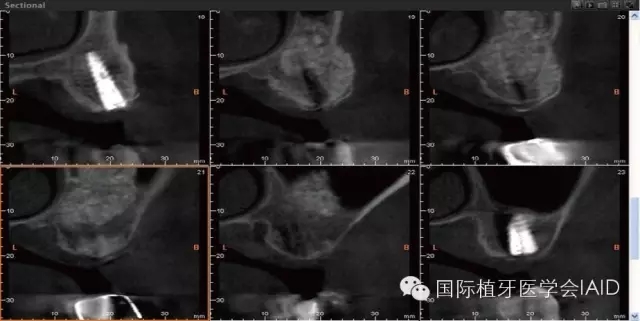

在植牙手術(shù)執(zhí)行之前,需要進行全口檢查與軟硬組織的評估??谕馐嗄P团ccone beam CT資料搜集有助于治療計劃的擬定。在石膏模型上進行diagnostic wax up有助于決定植體上假牙前后關(guān)系、頰舌側(cè)位置、咬合高度、及植體與植體上假牙的高度比例。使用Cone beam CT(CBCT)可以容易了解手術(shù)區(qū)硬組織條件,如Septum、骨頭高度及寬度、骨頭密度、神經(jīng)血管位置等。分析以上數(shù)據(jù)后,較容易得到可預(yù)期性的結(jié)果。

初期穩(wěn)定度在第一及第二類型的案例(>9mm; 6mm-9mm) 可以較容易達到,故通常以crestal approach進行手術(shù)。Lateral window術(shù)式在第三型(3mm-6mm)較被建議。 若是前三個類型的初期穩(wěn)定度達到35Mpa,可以考慮當次放置植體。若骨頭條件屬于第四型(<3mm),Lateral approach 比較建議使用,而植體可考慮等到Grafted Bone較成熟時再置入。(Fig. 1 & 2)術(shù)式的選擇與骨頭高度有密切的關(guān)系,當骨頭垂直高度小于3 mm(于兩顆植體中),植體應(yīng)考慮 Bone graft穩(wěn)定后再植入。

Lateral window的區(qū)域及范圍可借由CBCT和解剖構(gòu)造位置來決定。理想的window骨切線前緣及下緣位置應(yīng)離sinus底部(floor)其前緣(anterior wall)3-5 mm (Fig. 5 & 6)。